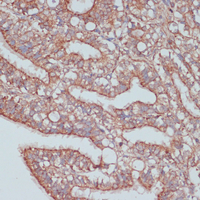

Immunohistochemical analysis of MOB4 staining in rat ovary formalin fixed paraffin embedded tissue section. The section was pre-treated using heat mediated antigen retrieval with sodium citrate buffer (pH 6.0). The section was then incubated with the antibody at room temperature and detected using an HRP conjugated compact polymer system. DAB was used as the chromogen. The section was then counterstained with haematoxylin and mounted with DPX.